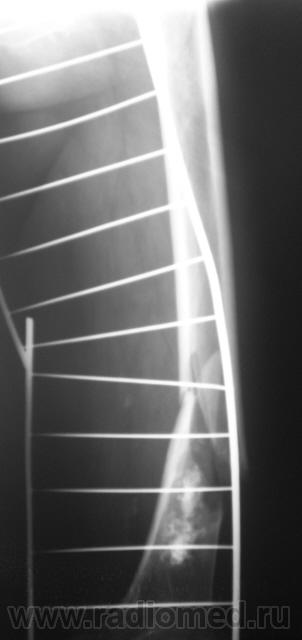

Ну, и, после "репозиции".

После репозиции дистальный отломок смещён латерально на ширину кортикального слоя.

Что это - не скажу (под рукой нет литературы). Но. 1.Процесс опухолевый - в средней части, по заднему контуру отмечается вздутие кости. 2.Относительно длительно текущий - вздутие достаточно протяженное. 3.Пока еще относительно доброкачественный - кортикальный слой созранен. 4. Многоузловой (мультифокальный) - не менее 3-х узлов/фокусов. В зависимости от возраста/пола/анамнеза вполне может быть метастатическим. 5.Перелом все-таки патологический - линия перелома проходит через верхнюю часть патологического субстрата.

Это может оказаться и безобидным обызвествлением костного мозга после инфаркта, хондромой или хондросаркомой. - Уроки Татьяны Валентиновны. Но вздутия не вижу - его в боковой проекции симулирует третий фрагмент в месте перелома. Ну а метастаз - маловероятен... Опять же - "горим" на сочетанной патологии...

Как по мне, так там наоборот, локальное (хотя и на достаточном протяжении) УТОЛЩЕНИЕ кортикального слоя по задней поверхности, хотя и в сочетании с умеренным вздутием.

Но наверно гипертрофия заднего полуцилиндра бедра - вряд ли заслуга локального процесса, скорее особенности осанки, и биомеханики нижней конечности - это очень длительное явление... Конечно тут без гистологии - пропадем...

хочу поддержать доктора Анатолия Шумакова: перелом вряд ли патологический, обызвествление костного мозга бедренной кости и вероятно стенок сосудов